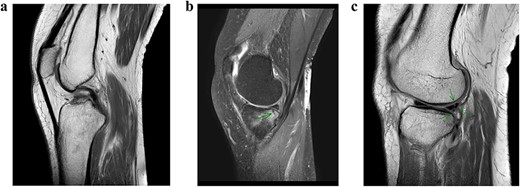

A conventional radiograph of the left knee showed no abnormalities (Fig. 1). An MRI scan was performed that confirmed an ACL tear accompanied by a grade 1 MCL tear, a lateral meniscal tear and a small incomplete fracture of the posteromedial tibia plateau (Fig. 2a–c). Arthroscopy of the knee was scheduled because of catching with persistent limited range of motion despite physical therapy 10 weeks after initial trauma.

Conventional radiograph of the left knee shows no abnormalities.

MRI scan of the left knee. (a) ACL rupture. (b) Small incomplete fracture of the posteromedial tibia plateau. (c) Partial lateral meniscal tear.